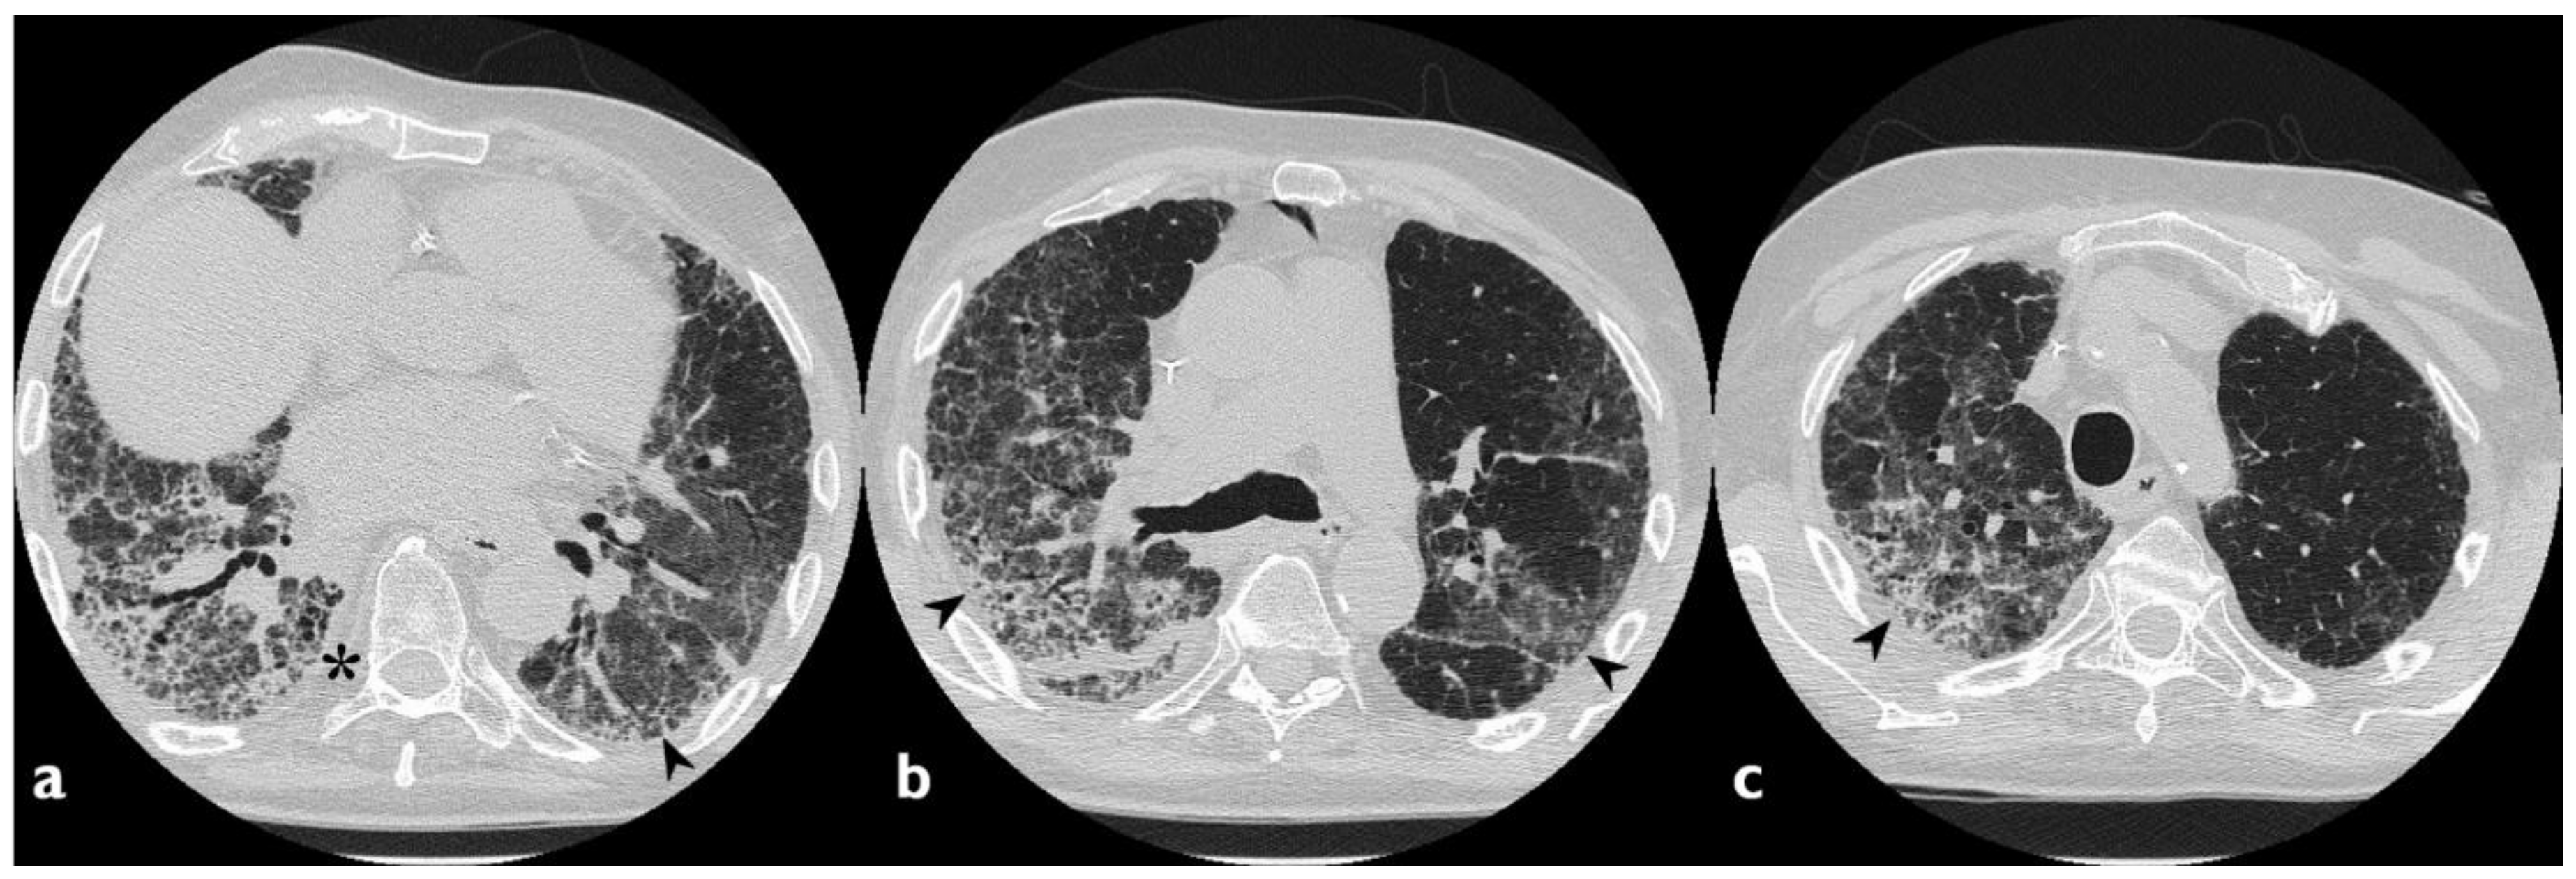

| HRCT Pattern | Associated Drugs |

|---|---|

| Fibrotic pattern | Nitrofurantoin (chronic toxicity), methotrexate, sulfalazina, rituximab, tocilizumab, bleomycin, busulfan, cyclophosphamide (chronic toxicity), amiodarone (form with fibrous course), tocainide, cocaine |

| Organizing pneumonia | Nitrofurantoin (chronic toxicity), methotrexate |

| Mosaic pattern | Nitrofurantoin (acute toxicity), methotrexate, sulfalazina |

| Isolated ground glass | Rituximab, tocilizumab, cyclophosphamide (acute reaction), amiodarone (initial stage), cocaine |

| Alveolar hemorrhage | Penicillamine, rituximab, cocaine |

| Pulmonary edema | Acetyl-salicylic acid, mitomycin |

| Pleural effusion | Sulfonamides, methotrexate |